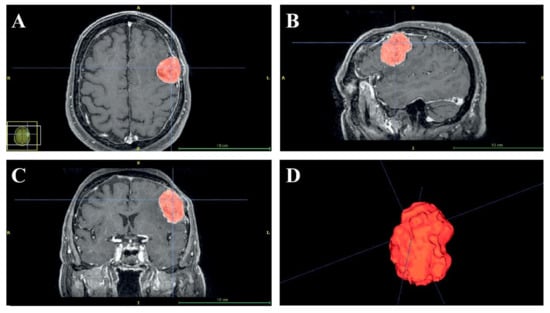

The preoperative (Figure 2) and the post-operative MRI sequences (axial spoiled gradient recalled acquisition in the steady-state (SPGR) sequences with a 0.5 × 0.5 × 0.6 mm resolution) were segmented using a semi-automatic tool, the “EndoCAS Segmentation Pipeline” (Pisa, Italy) integrated in the ITK-SNAP 1.5 open-source software (University of Pennsylvania, PA, USA), to generate the 3D virtual meshes of the patient face, skull, brain and meningioma.

Figure 2.

Semi-automatic segmentation of the preoperative axial (A), sagittal (B) and coronal (C) images using the EndoCAS Segmentation Pipeline. A 3D image reconstruction of tumors (D).